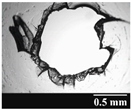

| Capsule Type | Time | RSC (%) | Area of Capsule Puncture (mm2) |

|---|---|---|---|

| GEL | Before storage | 15.26 ± 0.18 | 0.60 ± 0.16 |

| 1 month | 10.31 ± 0.21 | 0.74 ± 0.11 | |

| 3 months | 7.23 ± 0.28 | 1.01 ± 0.28 | |

| 6 months | 6.68 ± 0.12 | 1.14 ± 0.38 | |

| GEL-PEG | Before storage | 11.87 ± 0.09 | 0.54 ± 0.10 |

| 1 month | 10.68 ± 0.32 | 0.84 ± 0.12 | |

| 3 months | 8.74 ± 0.15 | 0.89 ± 0.14 | |

| 6 months | 7.12 ± 0.12 | 0.92 ± 0.07 | |

| HPMC | Before storage | 5.98 ± 0.11 | 0.79 ± 0.05 |

| 1 month | 5.45 ± 0.09 | 0.79 ± 0.04 | |

| 3 months | 4.84 ± 0.13 | 0.86 ± 0.08 | |

| 6 months | 4.62 ± 0.02 | 0.88 ± 0.03 |